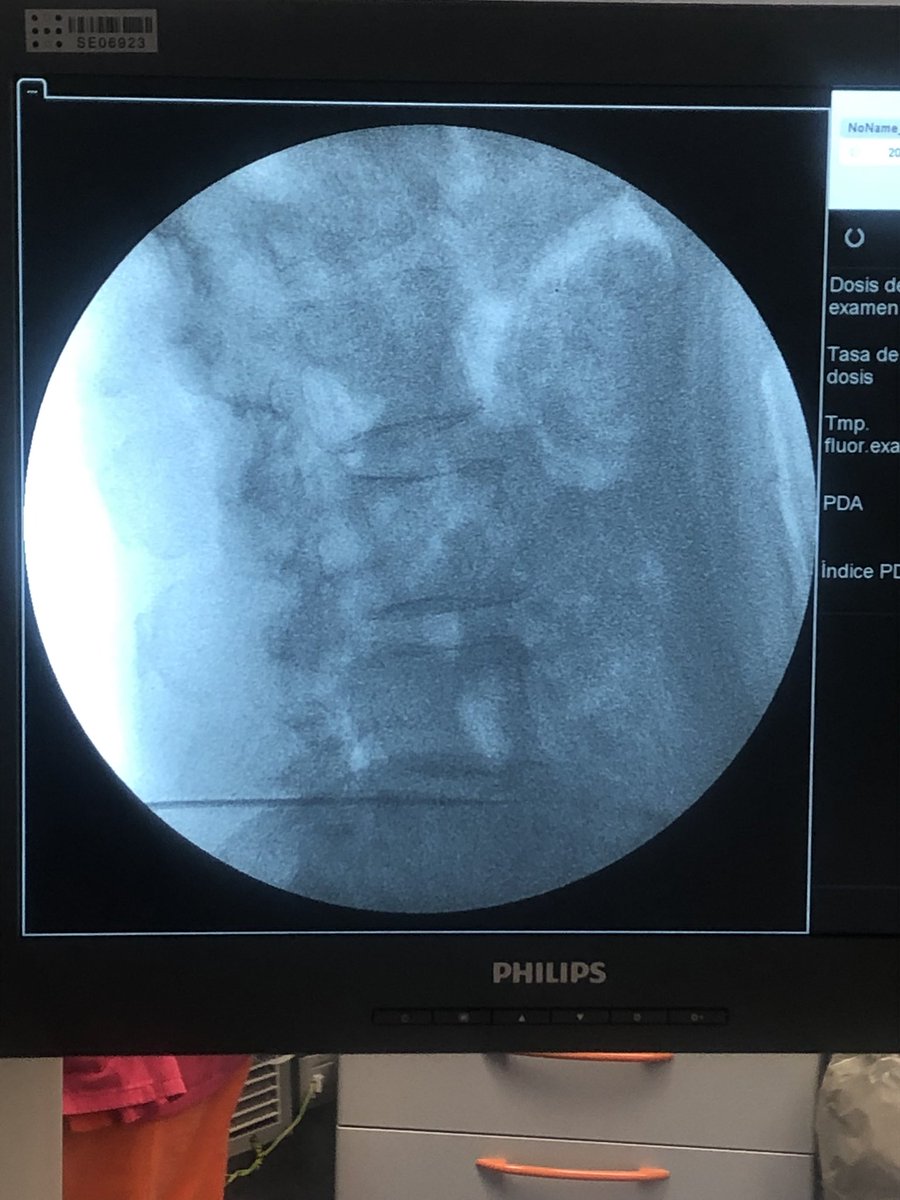

Implante de electrodo de ganglio para dolor de pared abdominal bilateral junto a la Dra Gomez y todo su equipo del hospital general de Navarra. Una alternativa al uso de opiáceos que, sin duda, mejorara la calidad de vida de esta paciente 👍👍